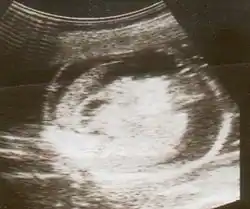

| An ultrasound showing a fetus with hydrops fetalis | |

Hydrops fetalis or hydrops foetalis is a condition in the fetus characterized by an accumulation of fluid, or edema, in at least two fetal compartments.[1][2] By comparison, hydrops allantois or hydrops amnion is an accumulation of excessive fluid in the allantoic or amniotic space, respectively.[3]

Hydrops fetalis can be diagnosed and monitored by ultrasound scans.[1] An official diagnosis is made by identifying excess serous fluid in at least one space (ascites, pleural effusion, of pericardial effusion) accompanied by skin edema (greater than 5 mm thick). A diagnosis can also be made by identifying excess serous fluid in two potential spaces without accompanying edema. Prenatal ultrasound scanning enables early recognition of hydrops fetalis and has been enhanced with the introduction of MCA Doppler.[7]